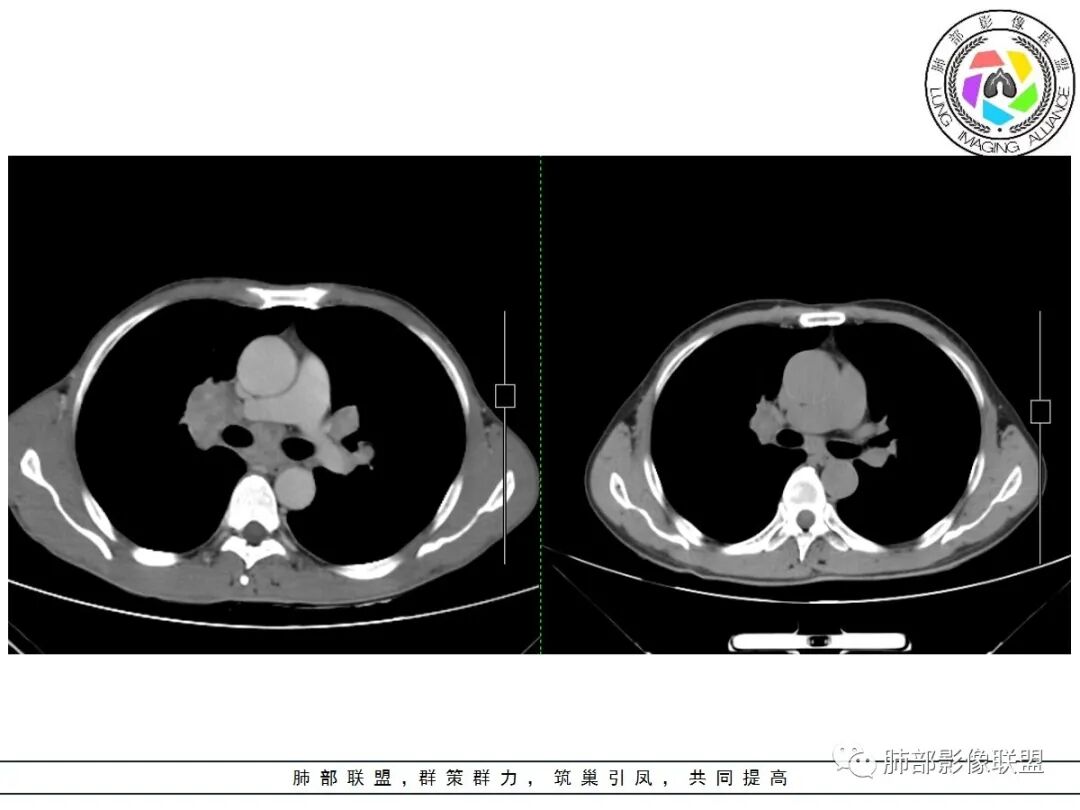

本例主要鉴别疾病:尘肺,小细胞肺癌伴转移,淋巴瘤,肺门淋巴结结核,血播结核,转移瘤等。

结节病是一种原因不明、多器官受累的肉芽肿性疾病。任何器官均可以受累,表现为双肺门淋巴结病、肺部浸润及眼部和皮肤病变。但以肺部、胸内淋巴结最常见。属于自限性疾病,预后较好。累及呼吸系统可有特定临床表现:以干咳多见,1/3-1/2的结节病患者可有呼吸困难、干咳、胸痛的表现,咳血罕见,后期纤维化时,可有气短、发绀。发热以低热为主。本例患者以干咳为主,糖皮质激素治疗有效。

结节病累及肺部表现:肺内多发结节,主要沿血管束、淋巴管周、小叶间隔、胸膜下分布,可呈串珠样改变。结节较大时可以融合;还可有实变及团块影;后期纤维化不可逆。

结节病的肺门及纵隔淋巴结增大也较有特点,较少融合,较坚硬密实,密度偏高,可钙化。偶或可以观察到低密度坏死,但较少且轻微。

双侧肺门明显的淋巴结肿大与常见肿瘤转移途径不一致。